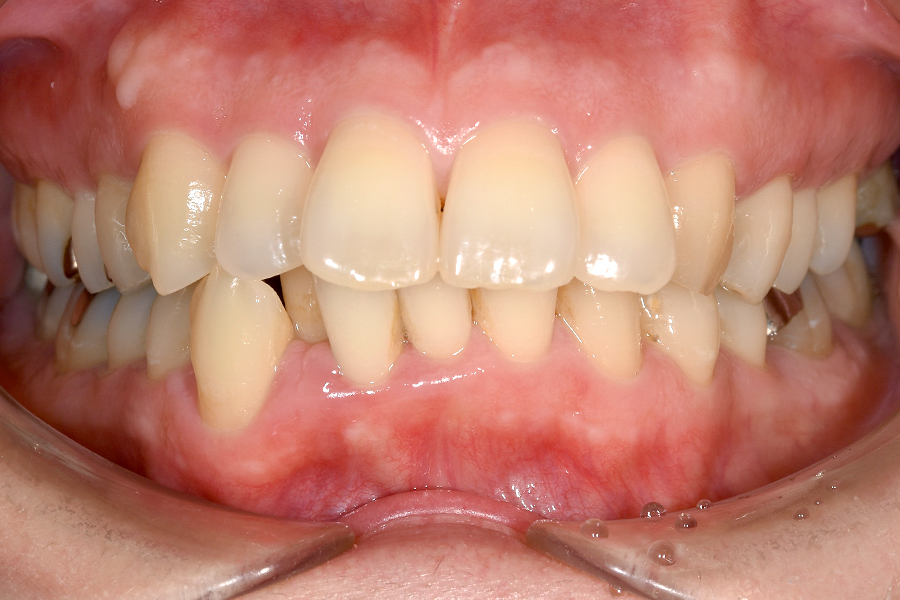

| 主訴 | 歯並びを治したい |

|---|---|

| 治療期間 | 5か月 |

| 治療費 | 部分マウスピース矯正(モニターキャンペーン)と ホワイトニングセット 422,596円(税込) |

| 治療内容 | 目立ちにくいマウスピース矯正 (非抜歯矯正) 歯と歯の間に隙間をつくることにより、歯列弓を広げながら治療を行いました。 また矯正用マウスピースをトレー代わりにし、ジェルを入れてホームホワイトニングを同時に行っております。 |

| 治療のリスク | ・後戻りする可能性があるのでリテーナーを最低でも矯正期間以上はつける必要があります。 ・ホワイトニング後、一時的に痛みが出る場合があります。 |